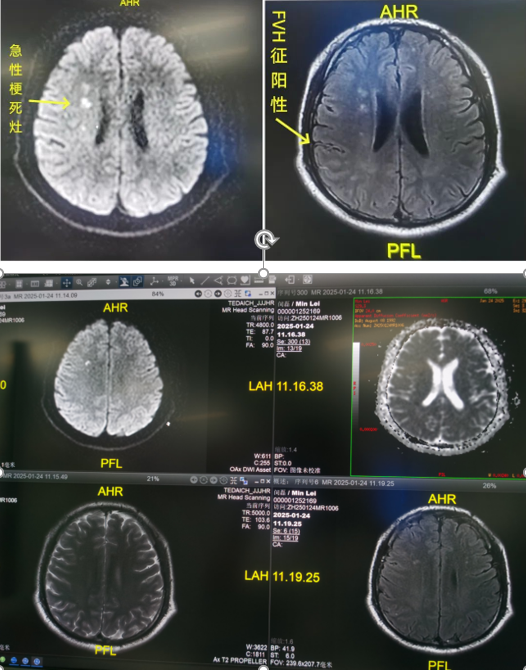

12:04,患者顺利抵达泰达医院神经科,救治进入关键阶段。经过进一步影像学检查,患者被确诊为右侧大脑中动脉夹层。这是一种极其凶险的病症,一旦血管完全闭塞,患者可能面临终身偏瘫。

泰达医院神经科主任郭再玉带领团队迅速制定手术方案,并争分夺秒开展手术治疗。凭借精准的术前评估、成熟的介入技术及团队默契配合,手术顺利完成,患者的生命被成功挽救,也大大降低了后续偏瘫的风险。